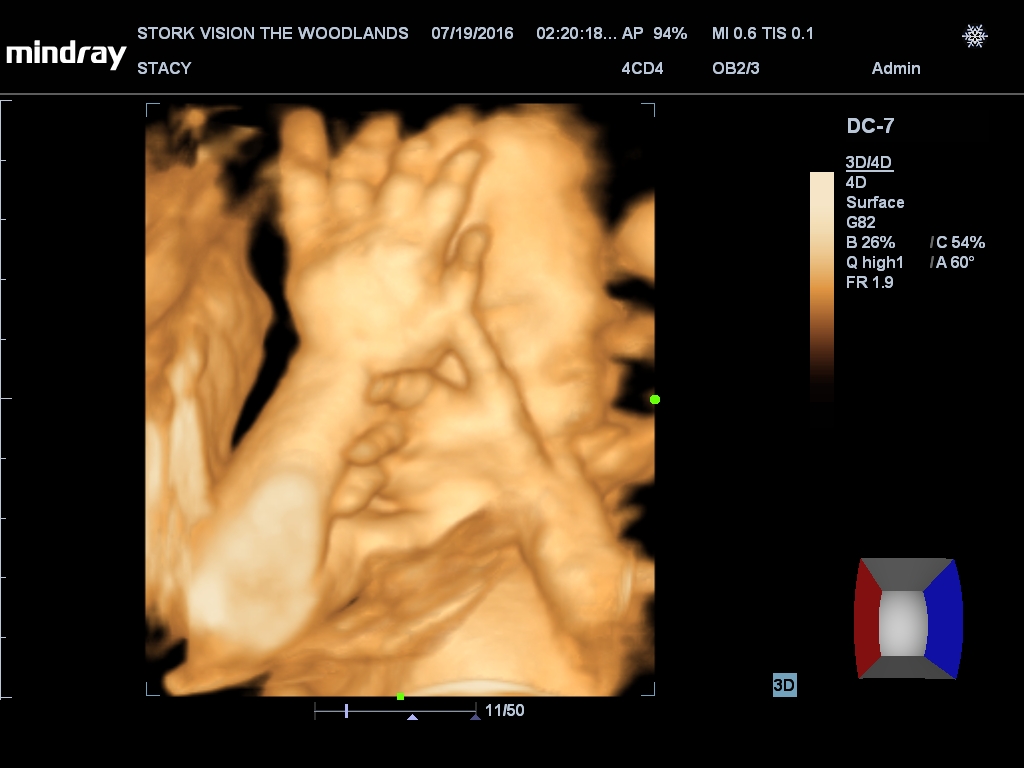

Best moment the week: Seeing Juliette on the 3D/4D ultrasound. So amazing!